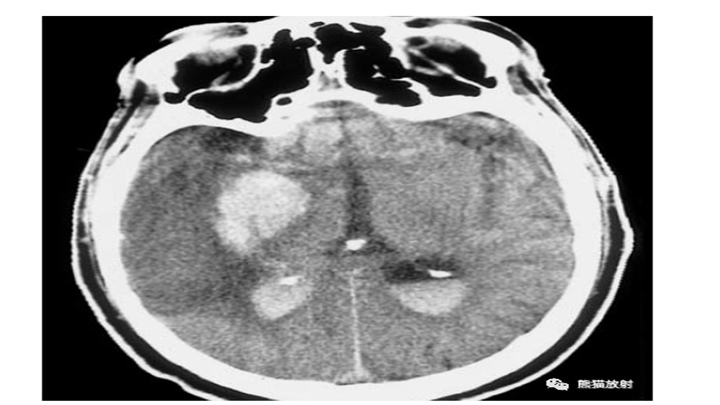

大量脑出血,累及左丘脑和基底节。明显的占位效应(中线结构向对侧明显移位)和脑室积血(同侧脑室变扁,右侧枕角积血)。然而,像往常一样,腹周水肿的数量仅限于周围边界。患者在数小时后死亡。